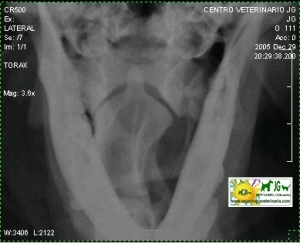

Radiografía simple (sin contrastes) | |||||||||

Radiografía digital (no digitalizada) de un cocker inglés mostrando el diente del axis. |